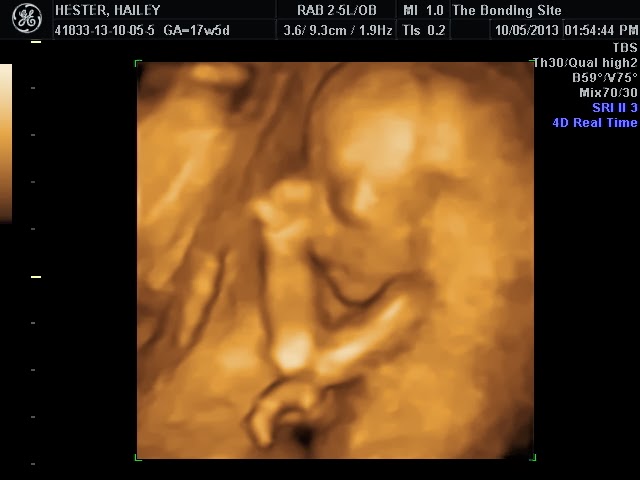

Our Ultrasound Experience - In Detail :)

I wanted to take some time to write in detail about the experience we had at the elective ultrasound last week.  I know in the years to come this will be a beautiful memory to come back and read about.

When it was finally our turn, the tech took Daniel and I back by ourselves because we wanted to share a special moment before the rest of the family came in.  When I laid down, the tech asked me if I was nervous.  I told her yes I was, because I wanted a girl, and he wanted a boy, so I was anxious to finally see what it was!  As soon as she placed the wand on my stomach,  the baby was upside down with butt directly facing the camera.  The tech immediately said "okay, well are you ready to know?"  Daniel squeezed my hand tight and we both said we were ready.  She smiled, and said, "Congratulations you're having a baby girl!"  I honestly don't quite remember how exactly things went after that.  I know that I covered my mouth with my hand, because I didn't want our family members to hear me and get a clue of what we had just found out.  My tears started coming and I just couldn't stop them!  I remember asking the tech multiple times, "Are you positive?"  And she kept snapping more photos and reassuring me that she was 100% sure.  At one point, I got overly excited and Daniel told me "Be quiet they're going to hear you!!!" When I finally regained composure, he went out to get the family, and the tech gave me a cloth to lay over my face because I knew if they saw my face I wouldn't be able to hide what the baby was.  They all filed in, and nothing was happening.....so I peeked out to figure out what was going on, and I could see that Daniel was having issues getting my Dad on Skype.  He finally got him on, and pointed the phone at the screen so Dad could see the baby.  The Skype only lasted about 10-20 seconds and shut off because the phone lost signal. :( So my mom called my Dad and put him on speaker phone, and the tech asked everyone if they were ready to know.  They quietly waited, and when she finally told them our baby was a girl, you would have thought we were at a football game from all the cheering. :)  I started crying all over again.  I wish my Dad could have been there in person, but it was nice to have him on the phone and be able to talk to him right when I found out!   After we finished the session, they gave us a DVD of the session, and also a CD with 52 images.  We also were able to choose 2 pictures to be printed.

It really was quite an experience. Definitely worth paying the money for.  I don't think either of us will ever forget the incredible feeling of seeing our baby on the big screen and being told we were having a little girl!!!

Mommy and Daddy can't wait to meet you, Little Miss Skylee Rae Hester.